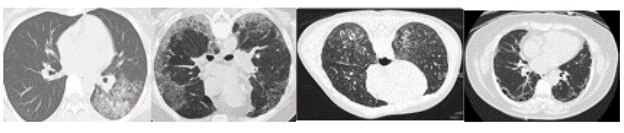

A chest CT dataset was used (Figure 2), which was obtained with different techniques and did not have standard features. Therefore, all images were pre-processed.